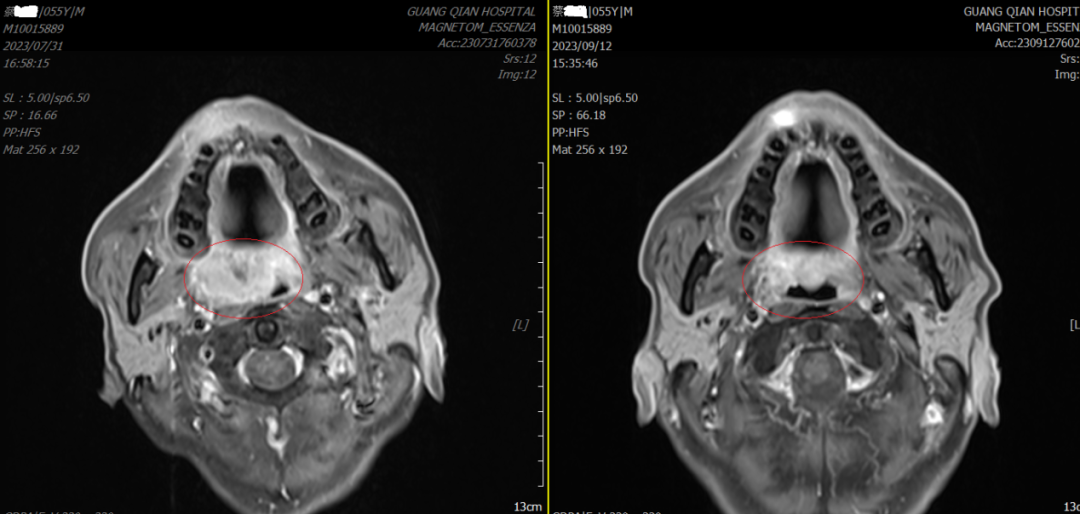

下圖是我院腫瘤放療一區(qū)邱家烷主治醫(yī)師在浙江省腫瘤醫(yī)院花永虹、姜鋒教授指導(dǎo)下完成的對蔡阿伯軟腭癌,誘導(dǎo)化療+免疫治療的治療效果圖,目前正在行同步放化療……